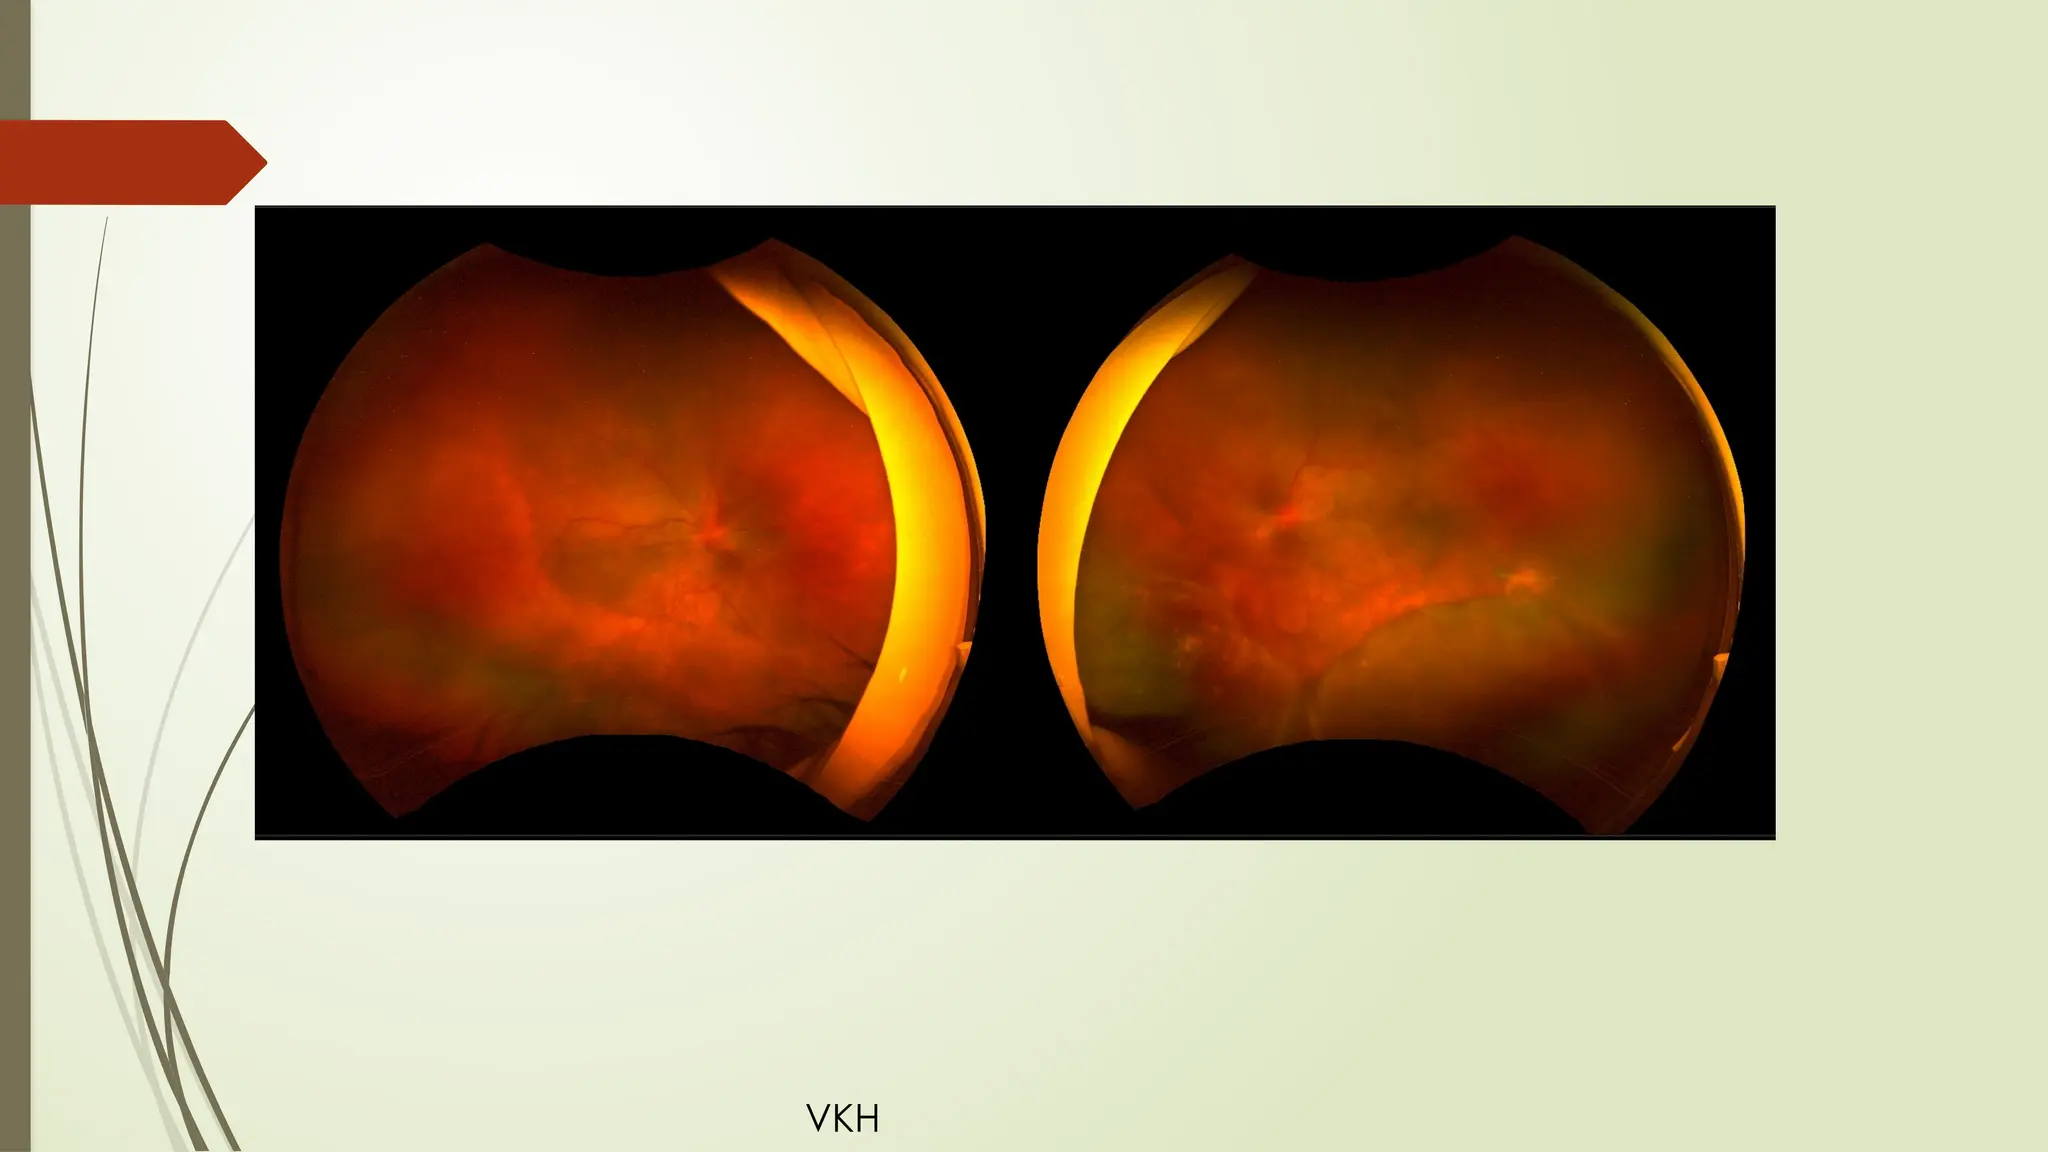

VKH

VKH – treatment with steroids and started on methotrexate

VKH – treatmentwith steroids and started on methotrexate